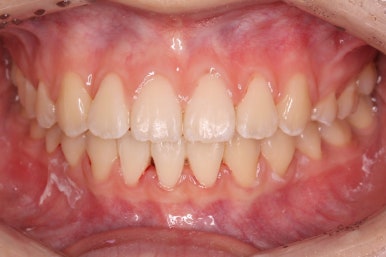

부산교정 키다리아저씨치과에 처음 내원하셨을 때의 입안 모습입니다.

윗니가 삐뚤어져 있고, 아래앞니 사이에는 틈이 듬성듬성 보입니다.

아랫니를 살펴보면 화살표 표시를 해둔 송곳니~송곳니 사이에 치아가 1개 모자랍니다. 원래는 4개의 앞니가 있어야 하는데, 3개 밖에 없었습니다. 이런 결손치아의 경우는 다음과 같은 문제가 생깁니다.

결손치아 부위에 틈이 생깁니다.

결손치아 주위 치아들이 제대로 서있지 못하고 기울어지게 됩니다.

위-아래 짝이 맞지 않아 중앙선이라든지 교합에 문제가 생깁니다.

이번의 경우 앞니가 하나 없는 경우여서 위-아래 앞니가 앞뒤로 간격이 멀어지게 됩니다.